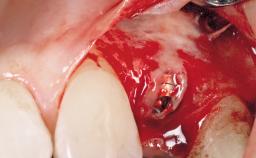

Immediate Flapless Placement of an Implant in a Maxillary Left Central Incisor Site

Type of Implants One-Piece

Abutment Type Customized

Placement Protocol Immediate implant placement

Tooth Site Maxillary incisor or canine

Socket Integrity Damage to one or more bone walls

Bone Volume Damage to one or more socket walls

Complexity Moderate